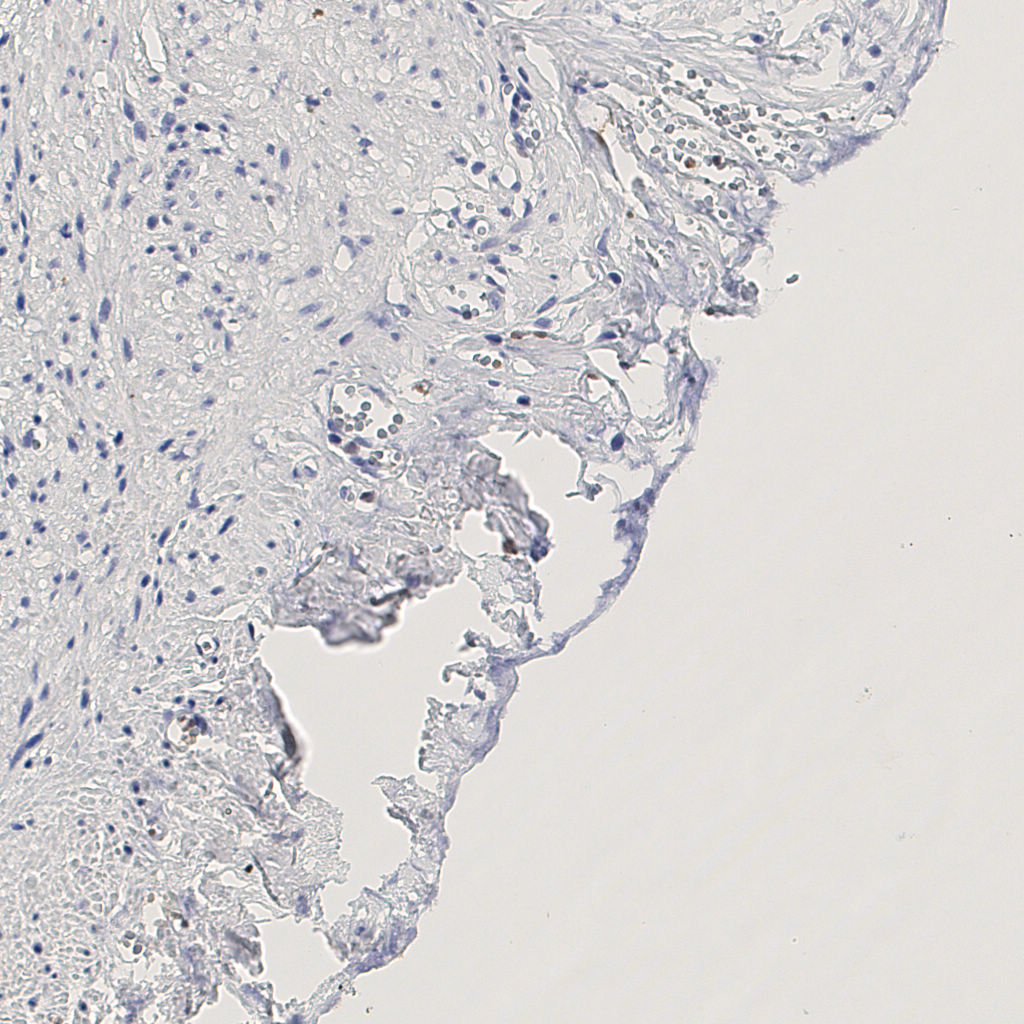

7.85%

Ki67 指数

阴 1104 阳 94